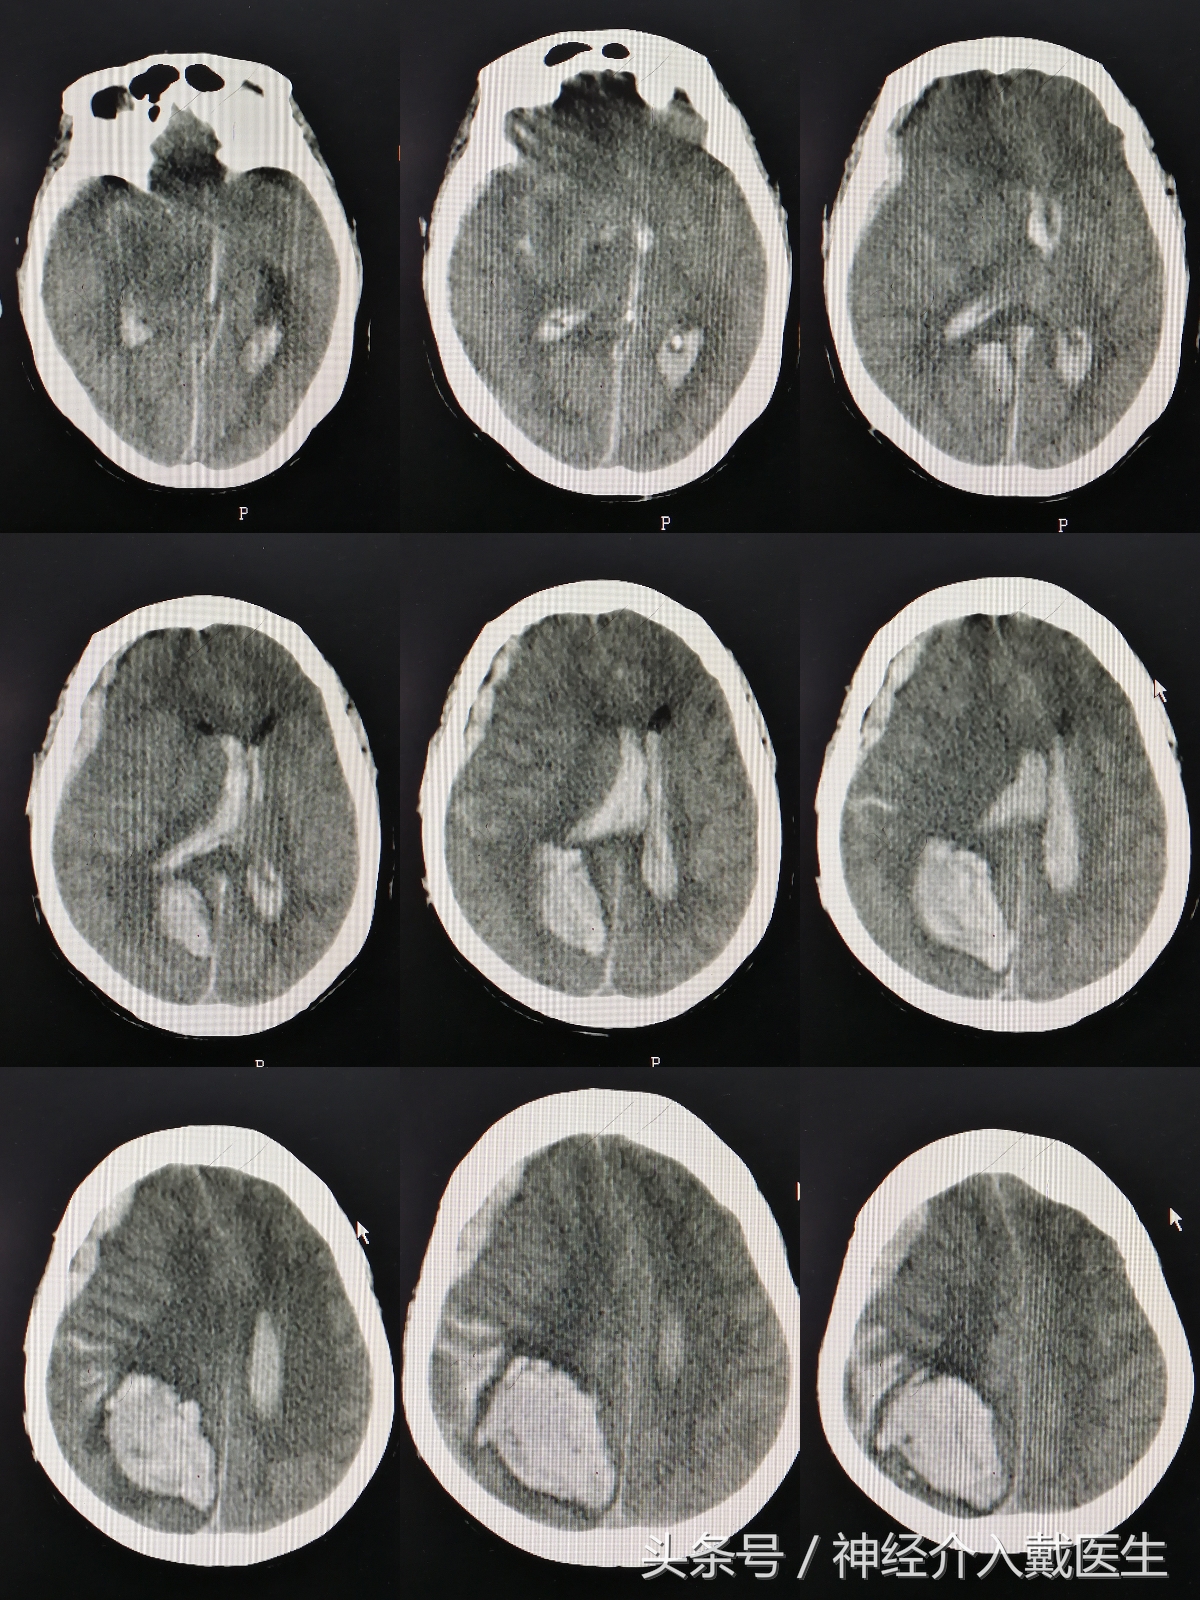

那是发生在去年12月23日晚上十一点多,随着救护车的一阵紧急呼叫,一名重型脑出血患者被送往重症监护室。谢某,女,77岁,因为突然神志不清1小时,呕吐2次,小便*禁失**入院。既往高血压病史20余年,血压最高220/120mmHg,冠心病10余年,平时低于一般活动即感胸闷,气促。入院时候血压230/120mmHg,双侧瞳孔已经散大,头部CT:右侧顶叶脑出血,脑内血肿,右侧额颞顶部硬膜下血肿,蛛网膜下腔积血及脑室出血,脑疝。

胸部CT:动脉粥样硬化,左心增大,肺部感染,心电图:偶发房早,多发室早,凭经验,脑内出血量这么大,超过70ml,这么快就发生脑疝的,人基本上难救的,向家属交代病情的危险性,做手术清除血肿和去骨瓣减压上唯一可能延长生命的方法,但是因为基础病变多,颅内出血多,手术风险是相当大的,可能死于手术台上,最好的结局就是植物人。病人的女儿是个老师,听我们说了之后,坚决要求尽最大努力抢救,并且和远在深圳的弟弟电话商量后,更是态度坚决,不管什么结局家属都能够接受,留下一个躯壳也行,并且一再保证,即使病人死了,也不会怪医生,让医生不要有后顾之忧。经过一个晚上的手术后,病人安全的下了手术台,

又经过多少个日日夜夜医生护士的努力,生命体征趋于平稳,目前已经转入普通病房,因为当时脑出血后导致的脑损伤太重,最近复查的头部CT,几乎满脑子都是缺血性改变。